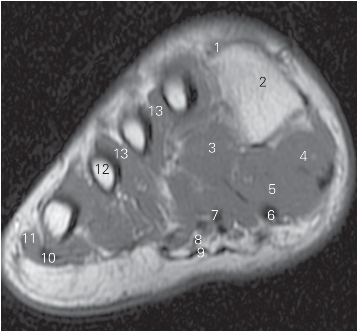

图5-52 经第一跖骨近端的横断层MR T1加权图像

1

长伸肌腱tendon of extensor hallucis longus

2 第一跖骨 1st metatarsal bone 3

展肌 abductor hallucis

4

收肌 adductor hallucis 5

短屈肌 flexor hallucis brevis

6

长屈肌 flexor hallucis longus 7 趾长屈肌 flexor digitorum longus

8 趾短屈肌 flexor digitorum brevis 9 足底腱膜 plantar fascia

10 小趾展肌 abductor digiti minimi

11 小趾短屈肌 flexor digiti minimi brevis

12 骨间足底肌 plantar interossei 13 第三跖骨 3rd metatarsal bone

14 第二跖骨 2nd metatarsal bone